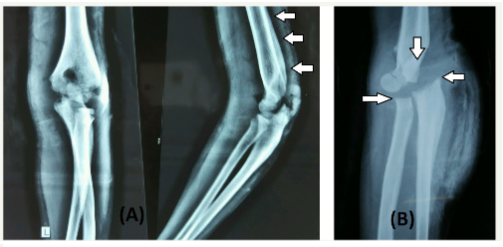

Figure 2: 2a: Radiograph at presentation showing periosteal reaction on posterior aspect of distal humerus (arrows).

2b: Radiograph of elbow at 3 months follow up showing destruction of radial head, olecranon, coronoid and traochlea.

These findings were suggestive of infectious pathology but lack of local signs of tenderness and presence of free movements at the elbow were contradicting each other. Aspiration of the elbow joint was planned and frank pus was aspirated from the posterior aspect. Diagnosis of osteomyelitis of the distal humerus with septic arthritis of the elbow joint was made and was planned for incision and drainage. The Distal humerus and the elbow joint were approached by posterolateral approach and about 100ml of pus was drained from elbow joint as well as from underneath of the triceps. The posterior surface of the distal humerus appeared rough with visible new bone formation. Copious lavage with normal saline was given and wound was kept partially open for free drainage. The patient was put on parentral antibiotics. The pus sent for culture sensitivity cultured Staphylococcus aureus and bone biopsy that was taken from distal humerus had features suggestive of osteomyelitis. The general condition of the patient improved postoperatively but there was persistent discharge from the wound without any signs of healing of the wound at three weeks following which a lavage and debridement was done and a low pressure vacuum assisted closure (VAC) dressings were used for a week after which signs of heeling and appearance of granulation tissue was seen. The wound heeled completely in next six weeks without any need for secondary procedure. At the final follow up range of motion at elbow was well maintained with little instability on stress tests. A radiograph of the elbow revealed complete destruction of the radial head, olecranon, coronoid and trochlea of the distal humerus (Figure 2). Despite the amount of destruction elbow function was relatively preserved because of absent pain sensations which allowed early range of motion at the elbow joint. Nerve conduction studies done at follow up had normal sensory and motor nerve conduction velocities. Sural nerve biopsy was planned but the parents did not give consent for the same.